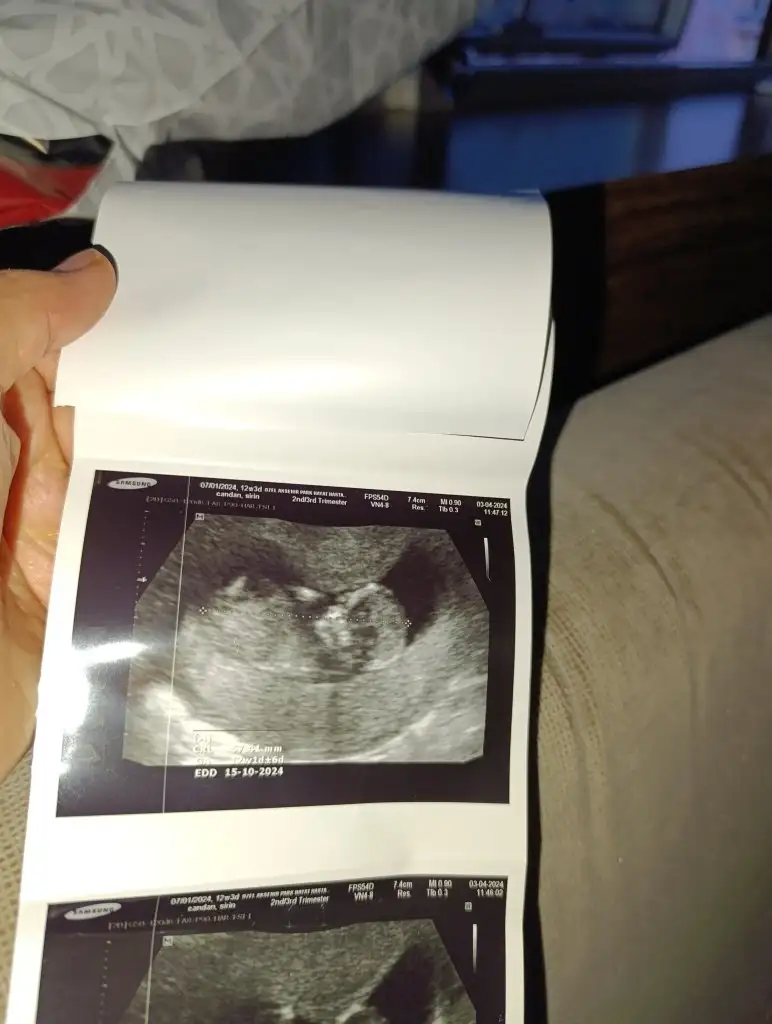

Bugün Dr kontrolum iyi geçti şükür ilk Dr girdik baktı ultrasonda o kalp atışını gözümle görene kadar galiba kalp krizi geciricem sandım o kadar korktum ki ama şükür kalp atışı iyi sadece uyuyor dedi açmışım diye sordu değilim dedim ama yinede bı cikolata ye gel dedi sonra tekrar gittiğimizde pozisyon değiştirmişti ama sakin bir bebek dedi ben şok oldum hep çok harketli olurlardı cinsiyete de baktı baktı pek benzetemedim dedi artık bir ay sonra ya dedi 😀 ikili tarama için kan da verdim hakkimizda hayırlısı🙏🧿

Bı de cinsiyet tahmini yapanlar var galiba birde bizim remimize bakıp tahminleri alalım 😀🧿